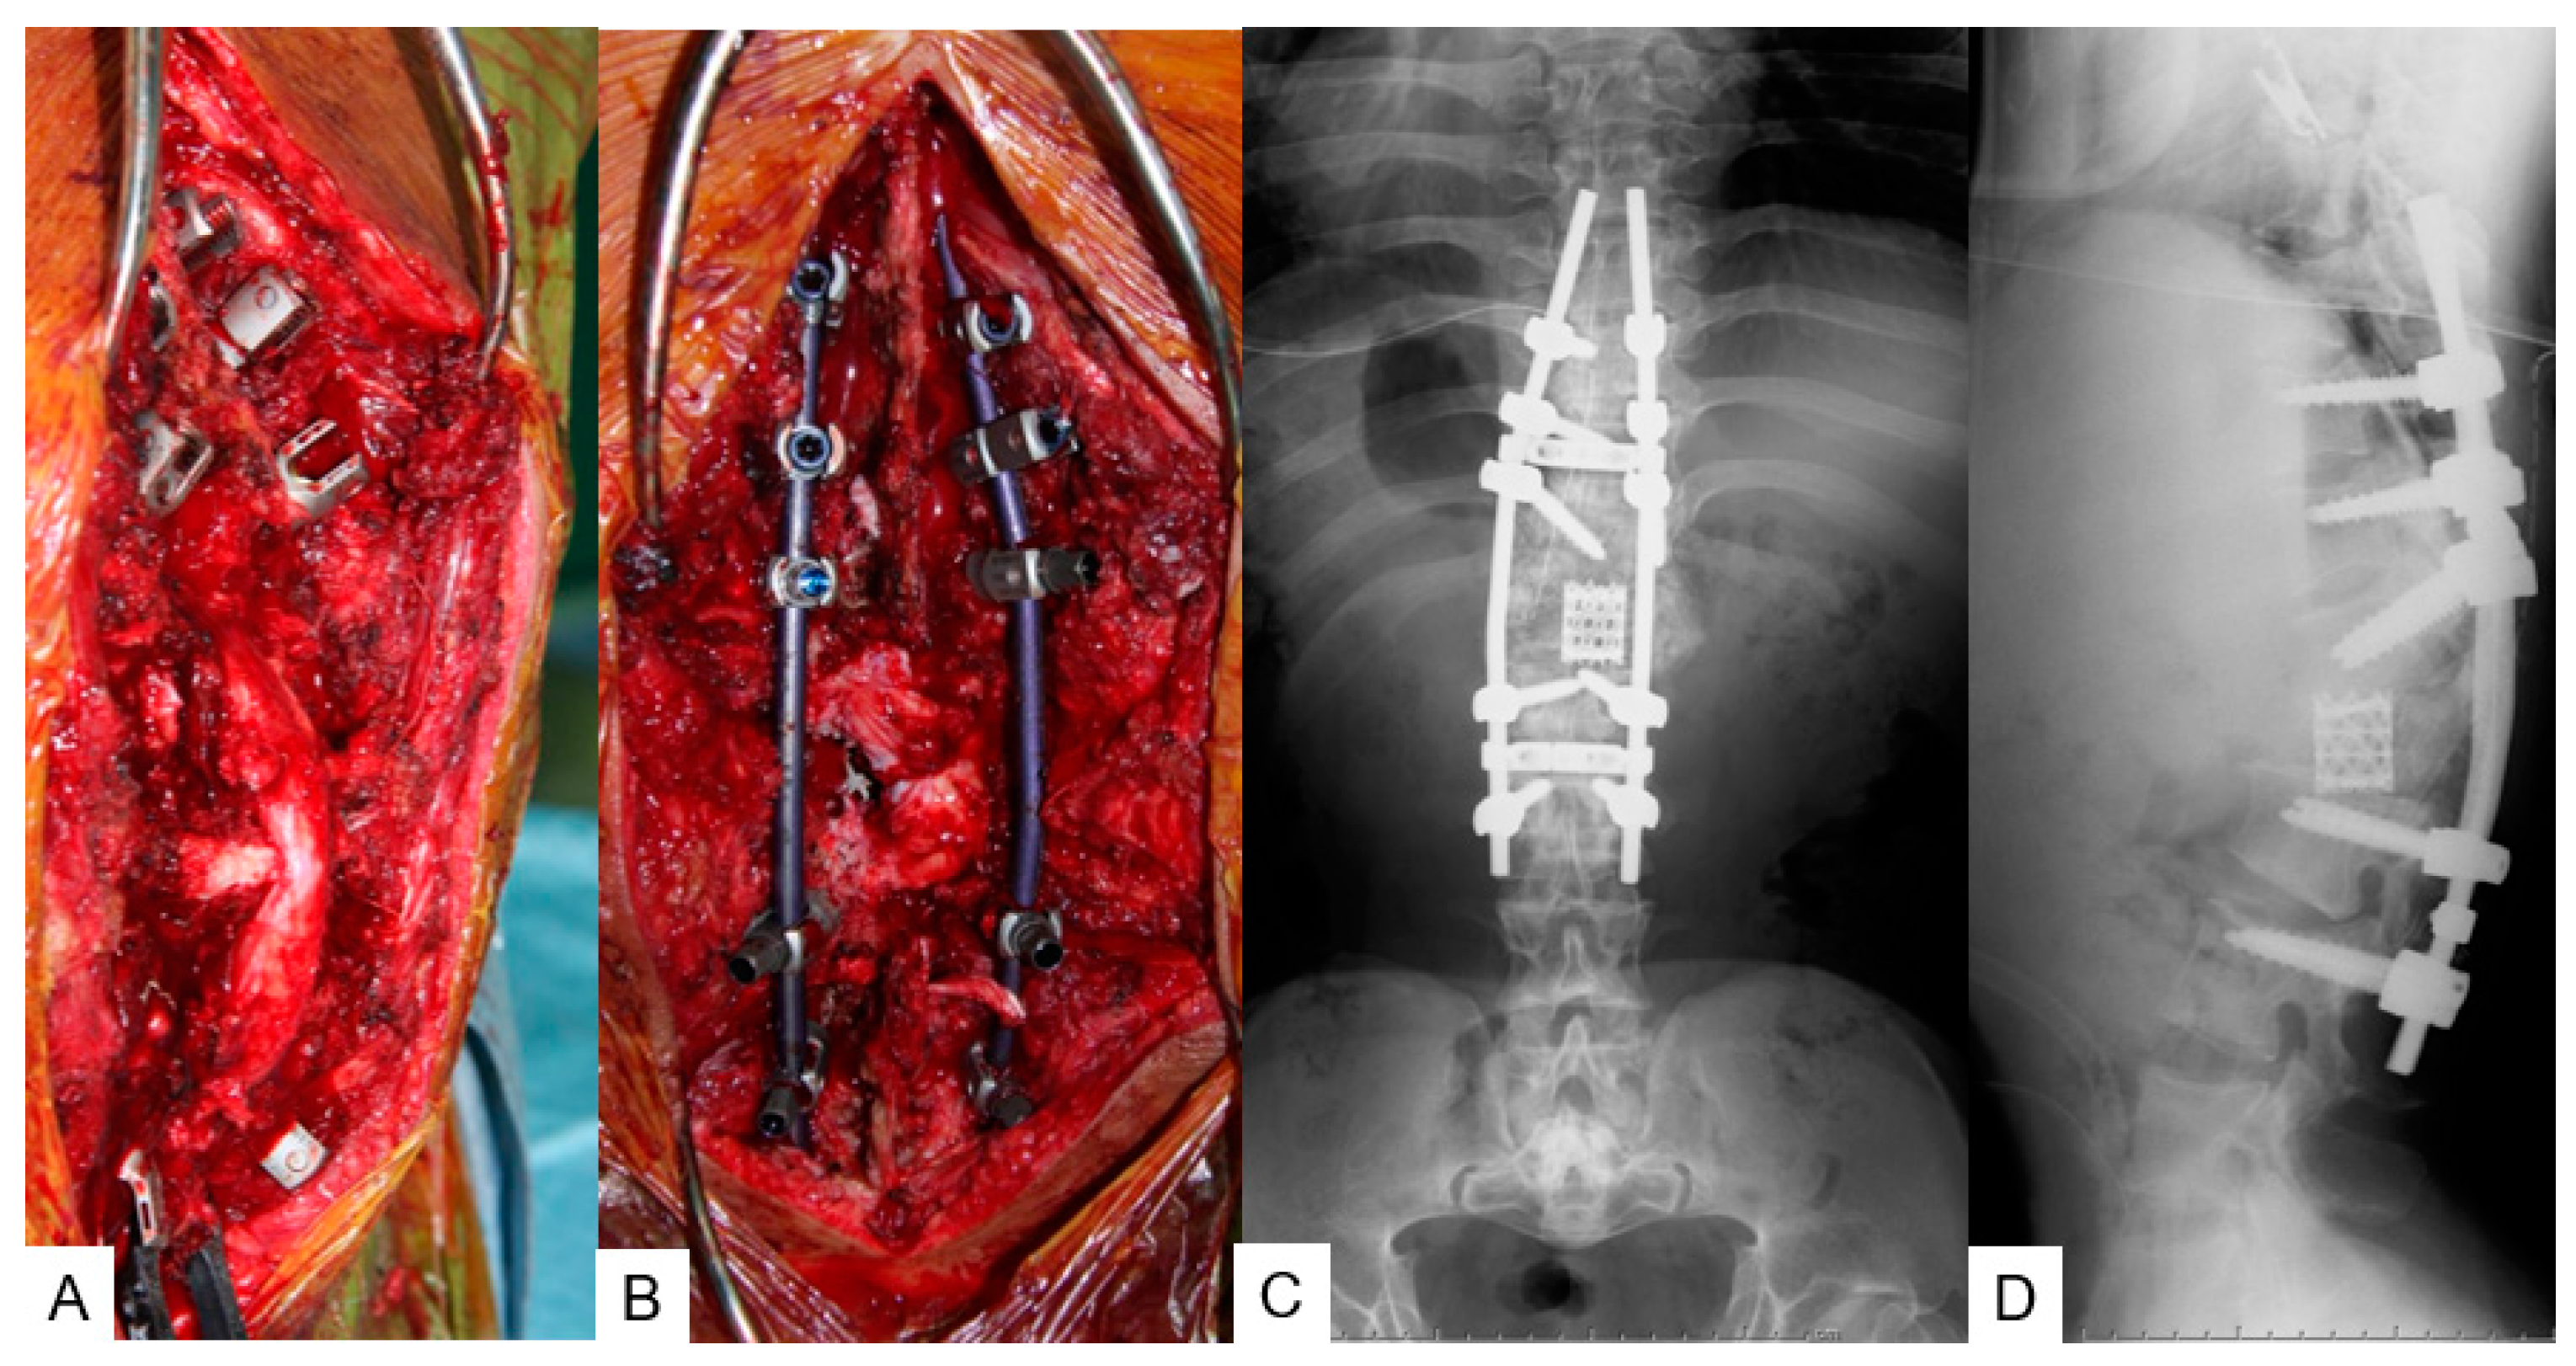

3.2.4. Surgery

3.2.5. Postoperative Imaging